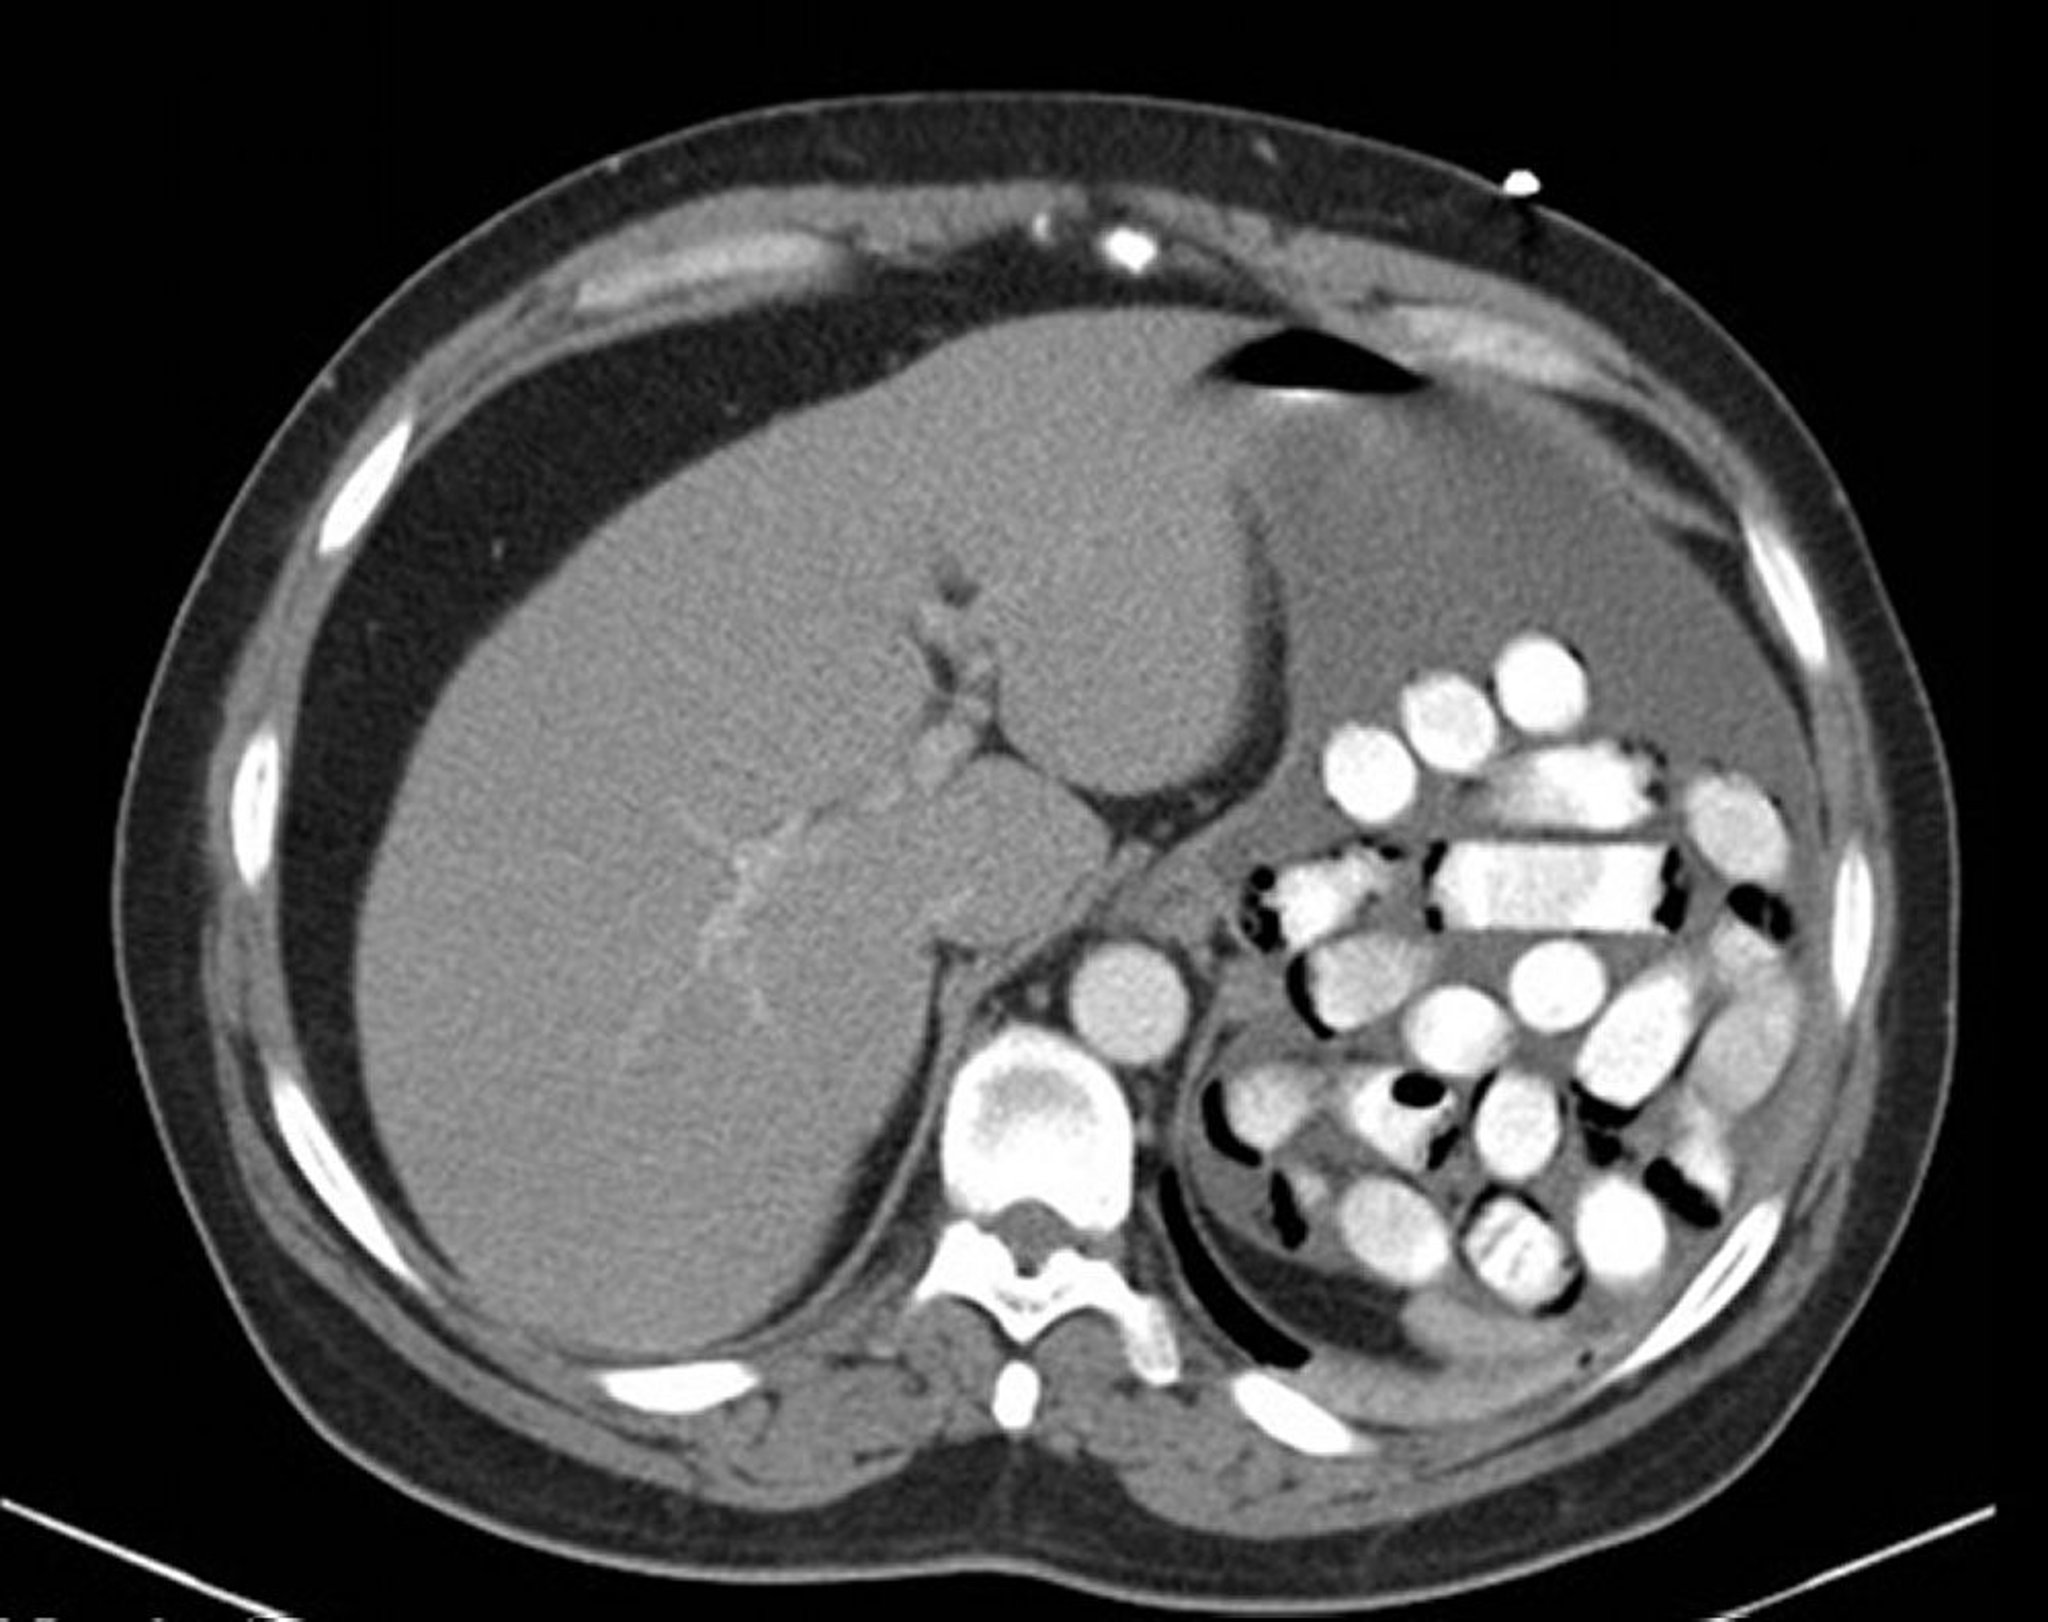

胃の中の異物(CT)

この画像には、胃の中にある薬物の包み(白い丸)が写っています。

Image provided by Alan Gingold, DO.